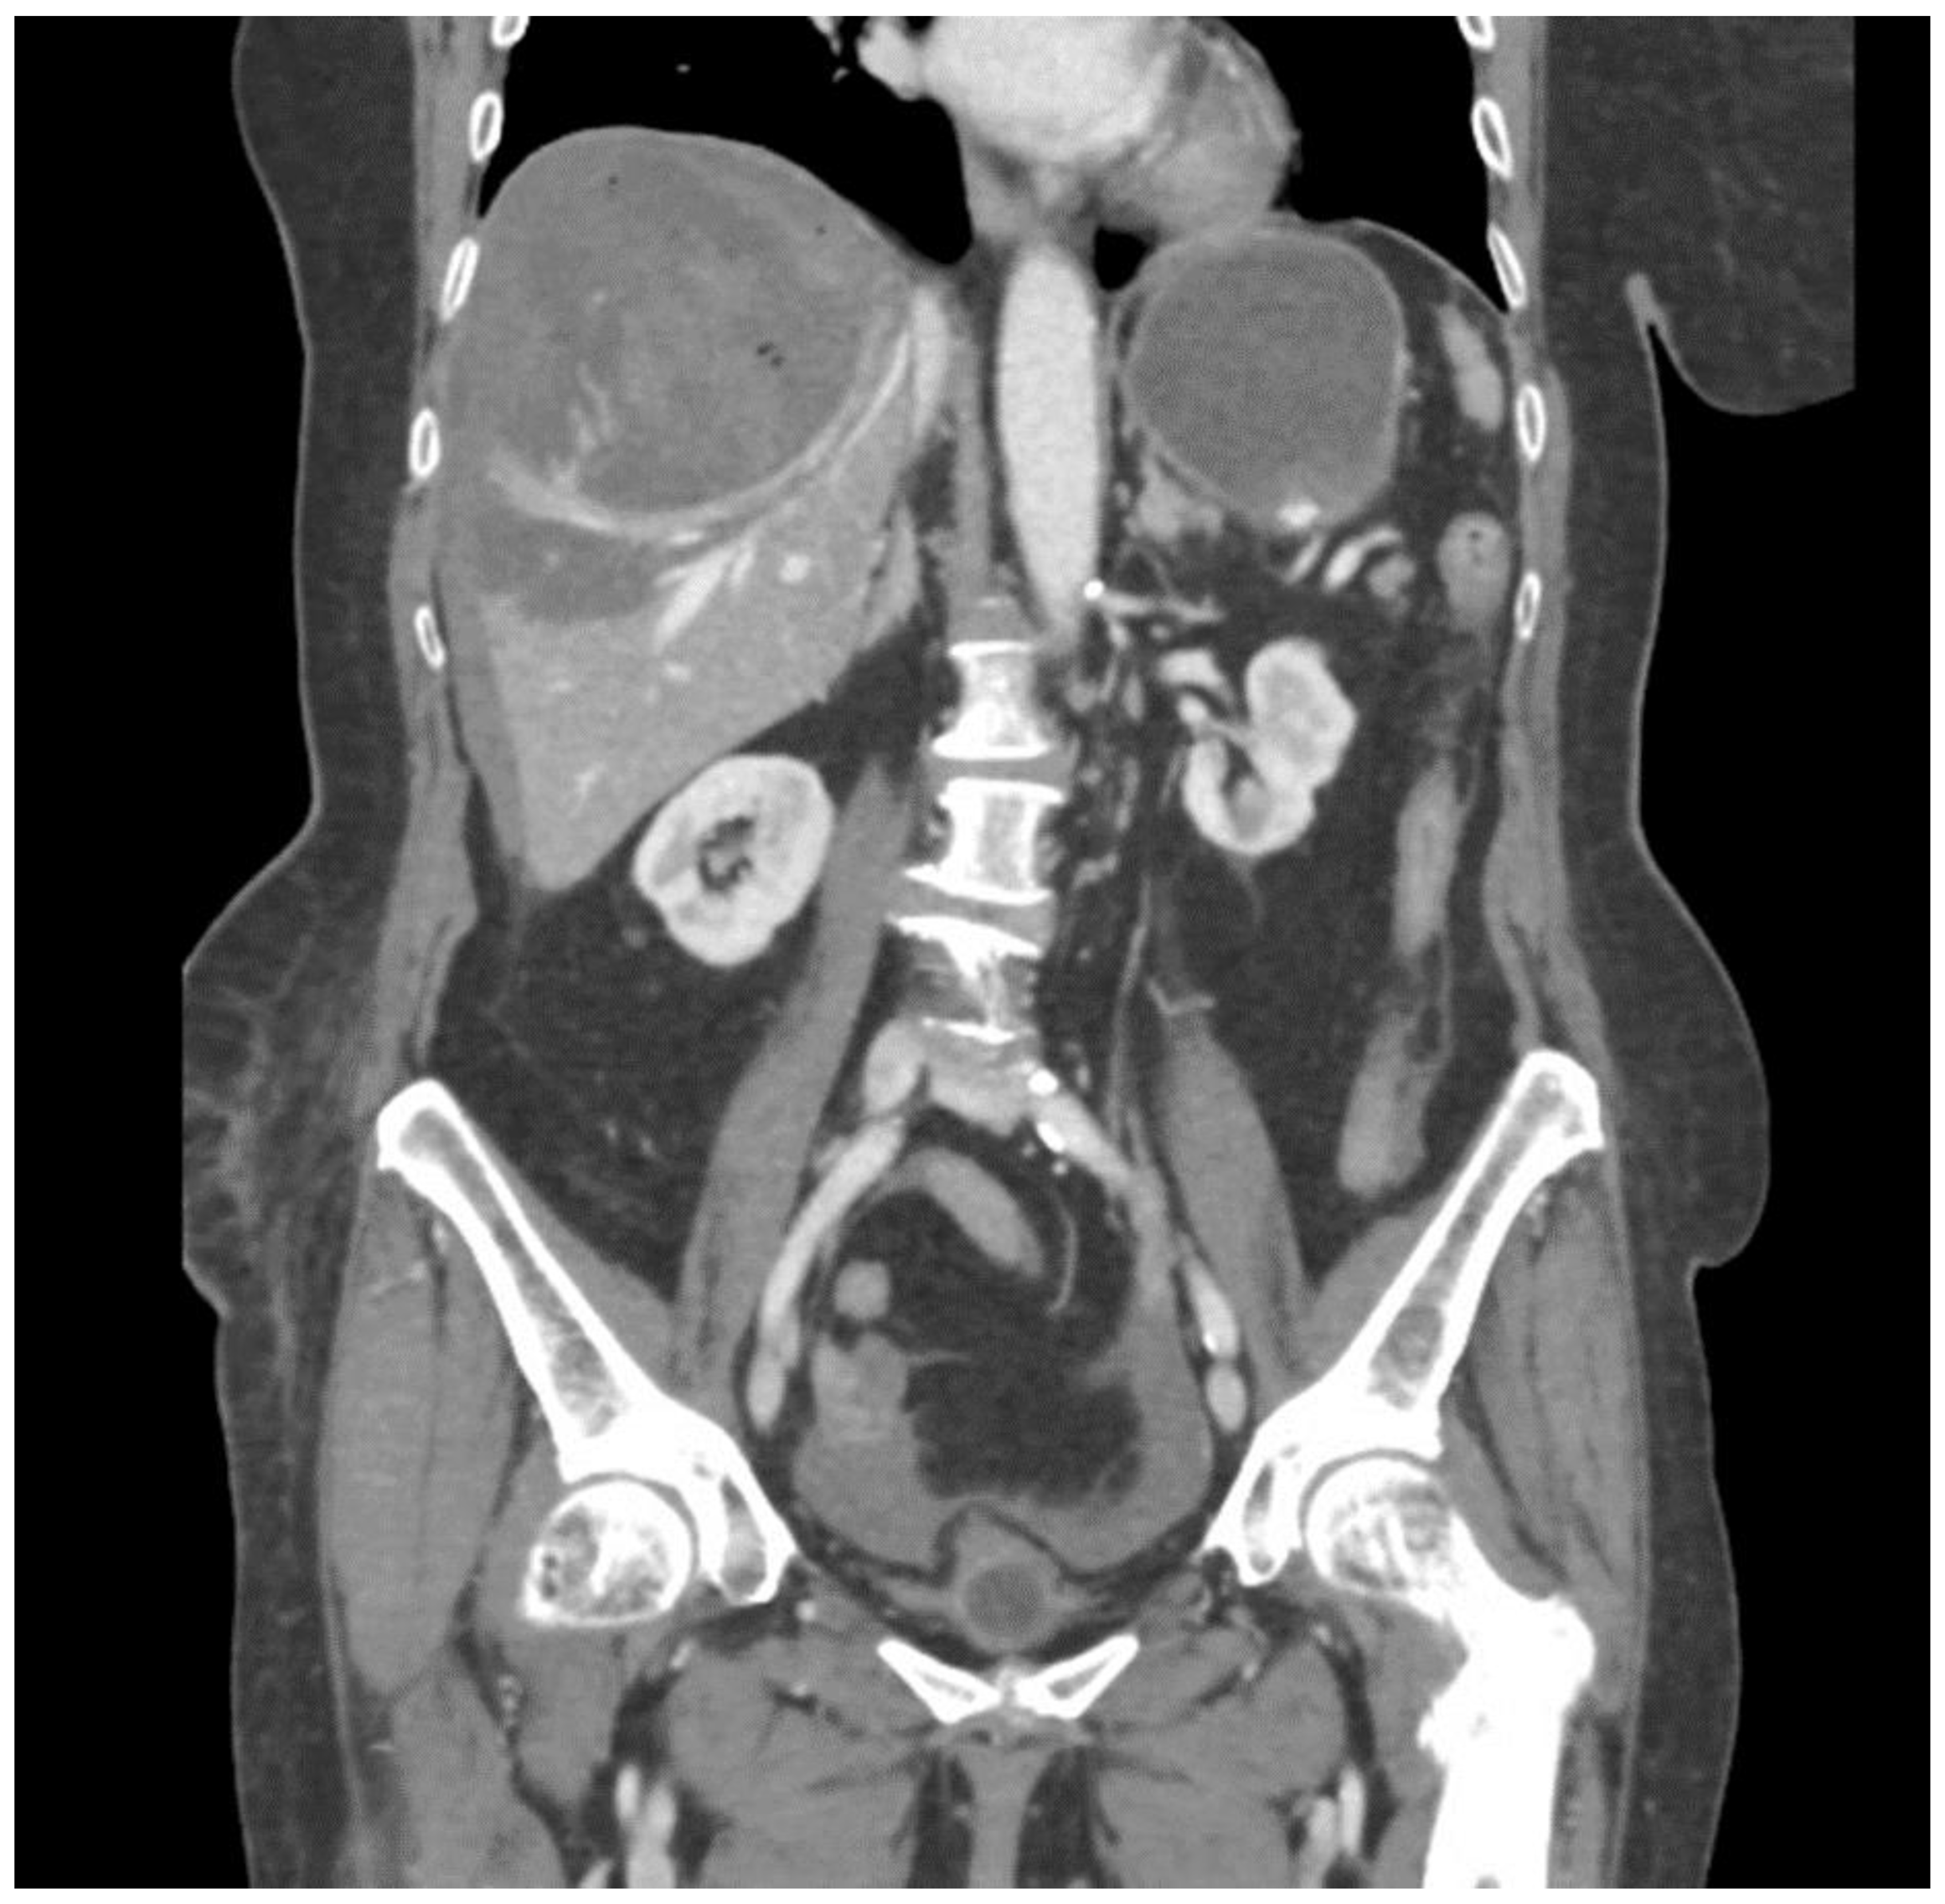

2. Case Report